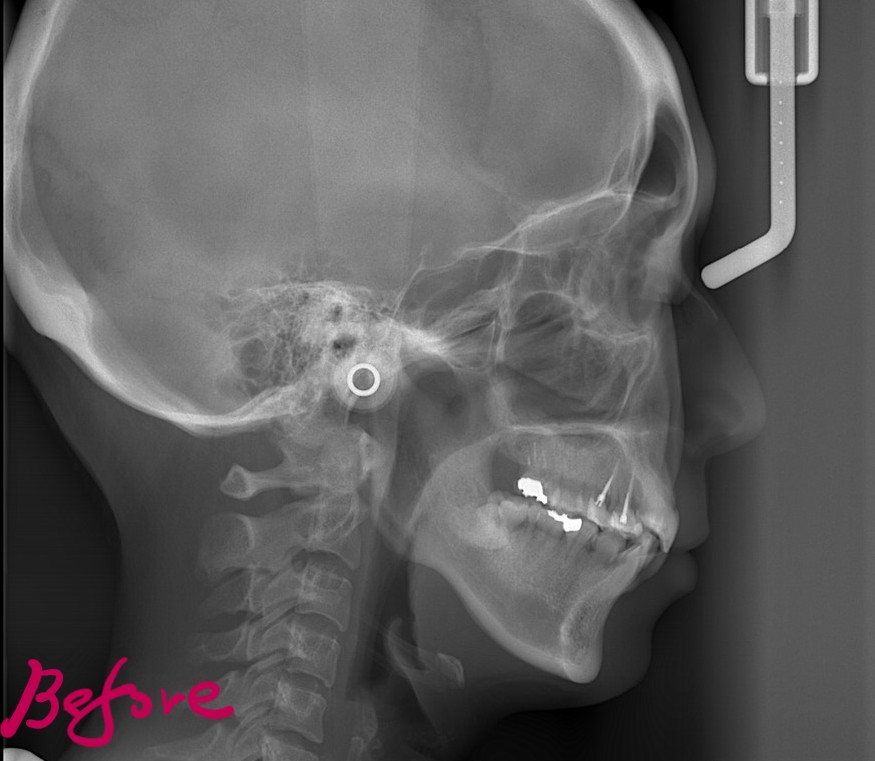

レントゲン写真で確認すると、

この患者さんの場合、

#1.顎と歯の不調和による叢生(重度)

#2.上顎前突(出っ歯)傾向

と診断しました。

レントゲン写真でも矯正治療前後を比較してみましょう